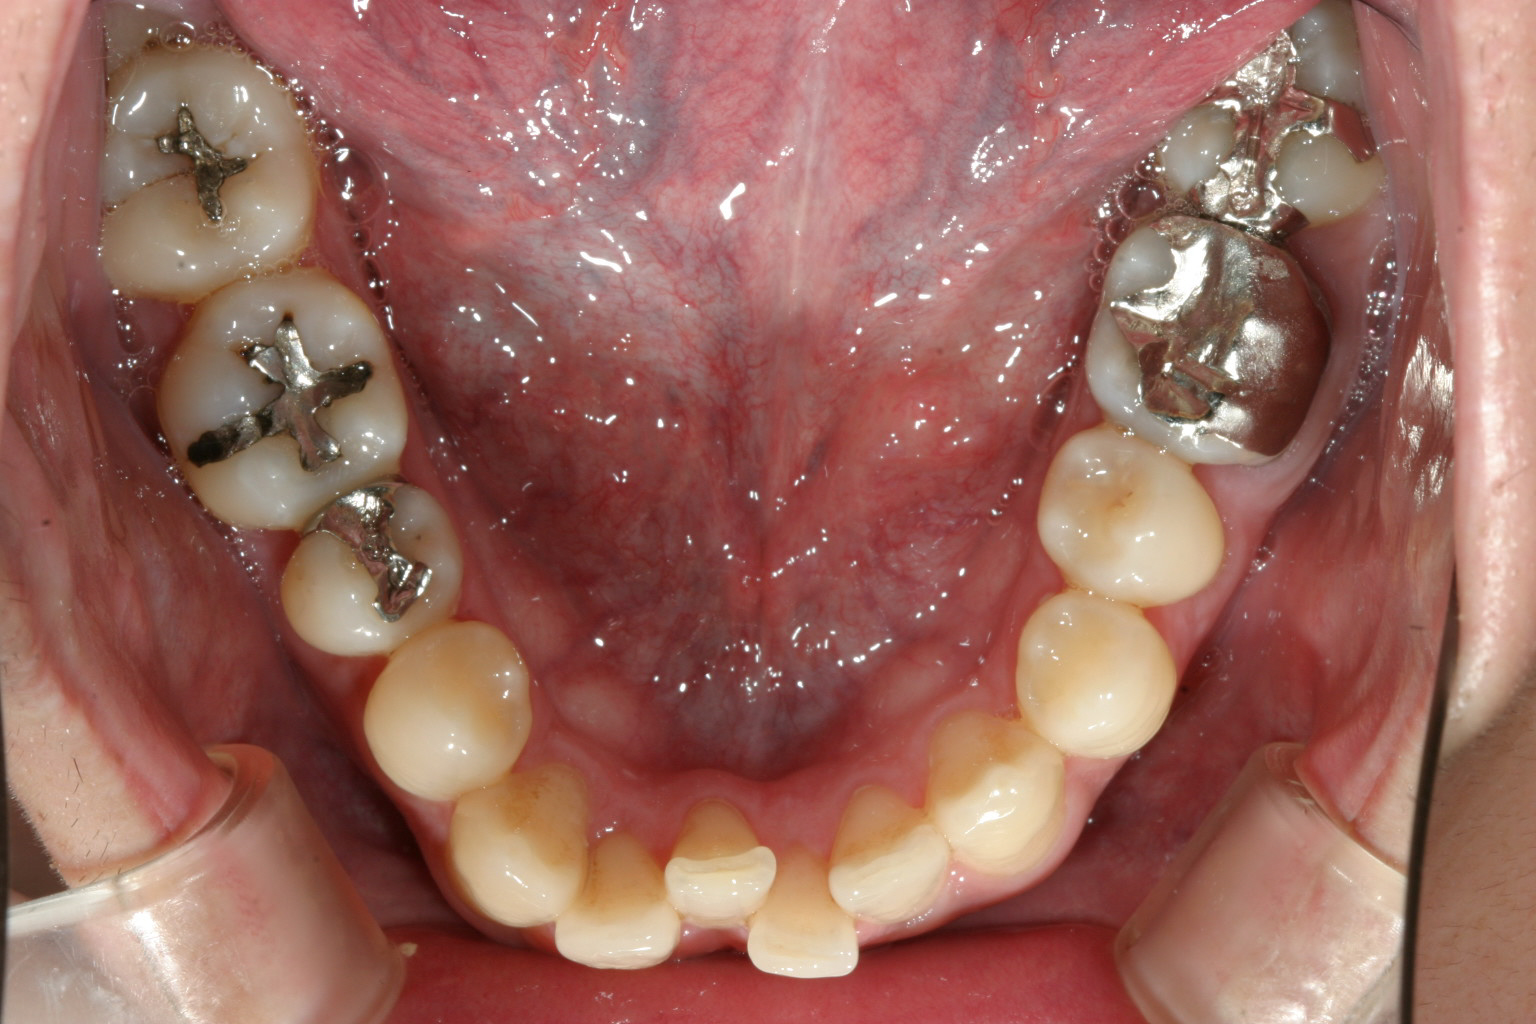

上顎がV字型の為下顎もV次型でその為叢生が存在します。

下顎も叢生も取れ綺麗に改善してます。

今回のケースは上下ともアーチ形状がV字の為スペースがなく4前歯が乱れている叢生にはよくあるケースです。

こういうケースの場合先ずアーチをU字に変える事から始まります。